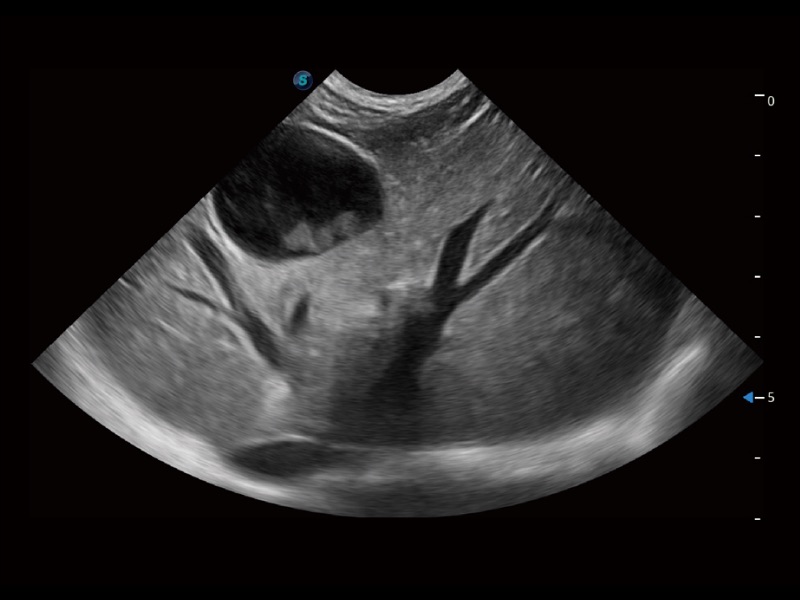

ProPet 70 进一步提升了微米成像算法,更加注重对基础原始图像的还原和保留,在有效减少斑点噪声、增强组织边界显示的同时,避免过度优化丟失真实的解剖信息。

ProPet 70专为动物医生设计,对不同的动物体型和生理结构作出了针对性的优化。通过动物影像专用软件,可满足个性化的应用需求,帮助动物医生获得更精确的诊断数据。

ProPet 70 全新的动物超声智能软件和丰富的探头群,为动物医生提供了高清晰度和精细分辨率的图像,无论在宠物、马科、畜牧还是实验室动物等应用中都可以轻松应对,为您的日常工作带来满意的体验。